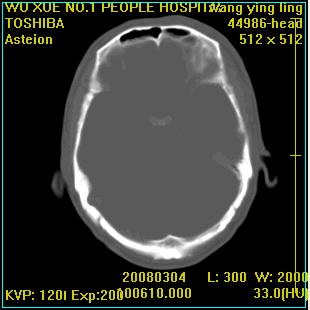

标题: CT12023:女,50岁,头部包块二月,伴轻微头痛,不伴发热。 [打印本页]

标题: CT12023:女,50岁,头部包块二月,伴轻微头痛,不伴发热。

这种病例还是比较多见,起源于颅骨板障,向颅内和颅外生长,考虑血管瘤或嗜酸性肉芽肿,要是有增强ct就好了。

多发溶骨性破坏,骨嗜酸性肉芽肿可能,转移瘤待排除,建议进一步检查。

破坏区边界较清楚,还是考虑良性病变---嗜酸性肉芽肿可能。

颅骨多处破坏伴软组织肿块,考虑为转移瘤可能性大。

病灶呈溶骨性骨破坏,考虑嗜酸性肉芽肿可能转移瘤不除外建议追查病史并进一步检查